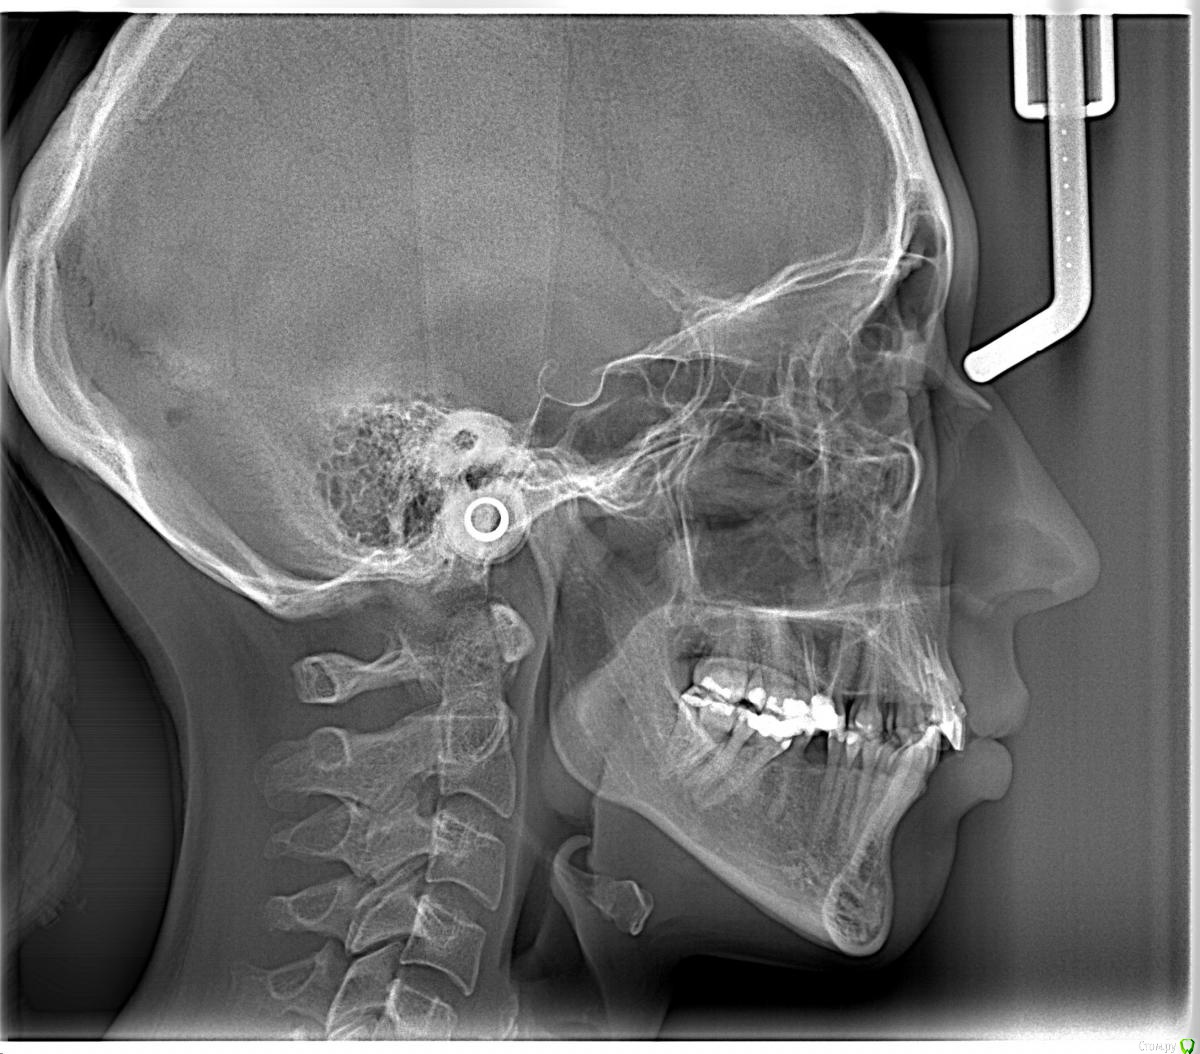

Opdihatop Опубликовано 24 февраля, 2017 Поделиться Опубликовано 24 февраля, 2017 И снова здравствуйте! Прошу совета еще по одному случаю. 28 лет, вертикальный рост, 2 класс. Вопрос тут в чем, реально ли убрать такой gummy smile на петлях и микроимплантатах? Пациентка направлена к хирургу для консультации по поводу импакции в/ч, но большим энтузиазмом по этому поводу не обладает. Ссылка на комментарий